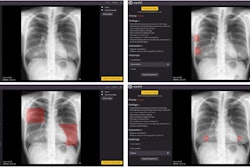

- Is chest x-ray about to be rendered obsolete by chest CT scans? Or will integration with AI allow chest radiographs to hold their own? Those questions were answered in another session.

Aside from our ECR coverage, it appears that researchers are calling for more “real-world” studies of AI algorithms designed for interpreting chest x-rays. Recently, a group in Spain tested a product called ChestEye (approved in the European Union in 2019) and found it provided less than what’s required for clinical implementation.